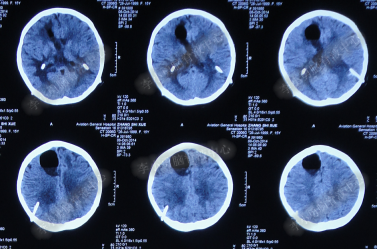

患者因恶心、呕吐伴头痛头晕,自行服药后无法自行缓解,于2014年5月29日就诊位于重庆的著名的三甲肿瘤医院,查全脑CTA和CT后诊断为“小脑蚓部占位伴幕上脑积水”(图-1、图-2)。

图-1:2014年5月29日全脑CTA

图-2:2014年5月29日头部CT